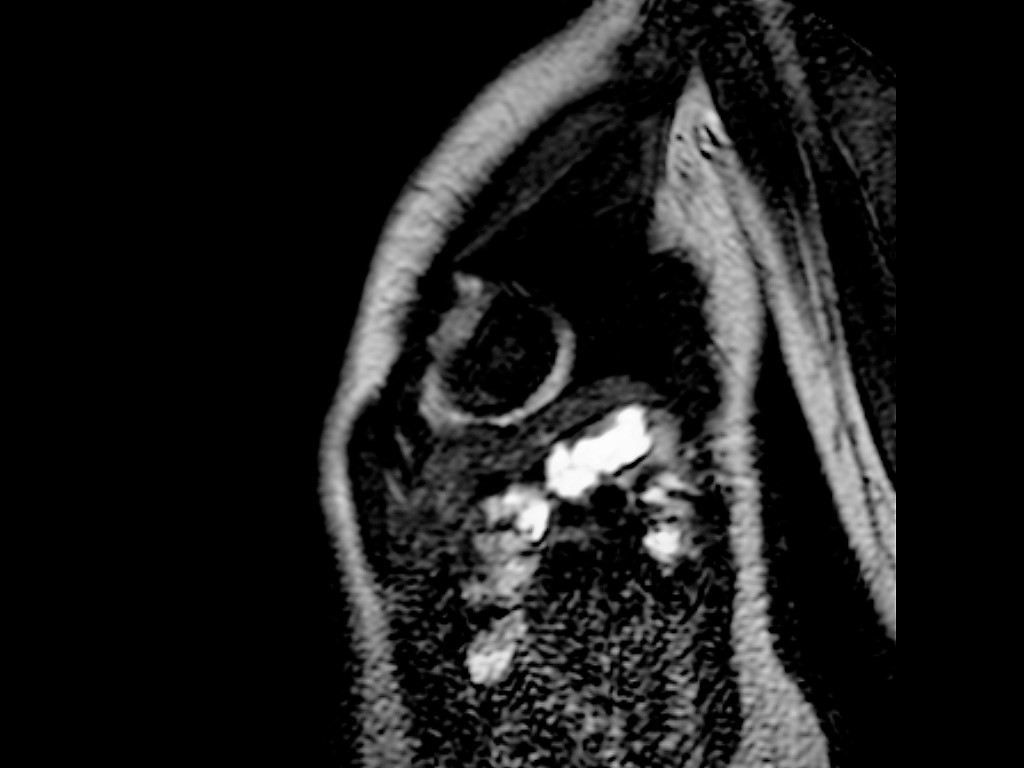

Se continuó estudios mediante RMI cardíaca observándose la misma cavidad contráctil observada en el ecocardiograma compuesta de las tres capas cardíacas. Se descartó la presencia de realce tardío de gadolinio. De esta manera se confirmó el diagnóstico de divertículo apical del VI.

RMI 1

RMI 2

RMI 3